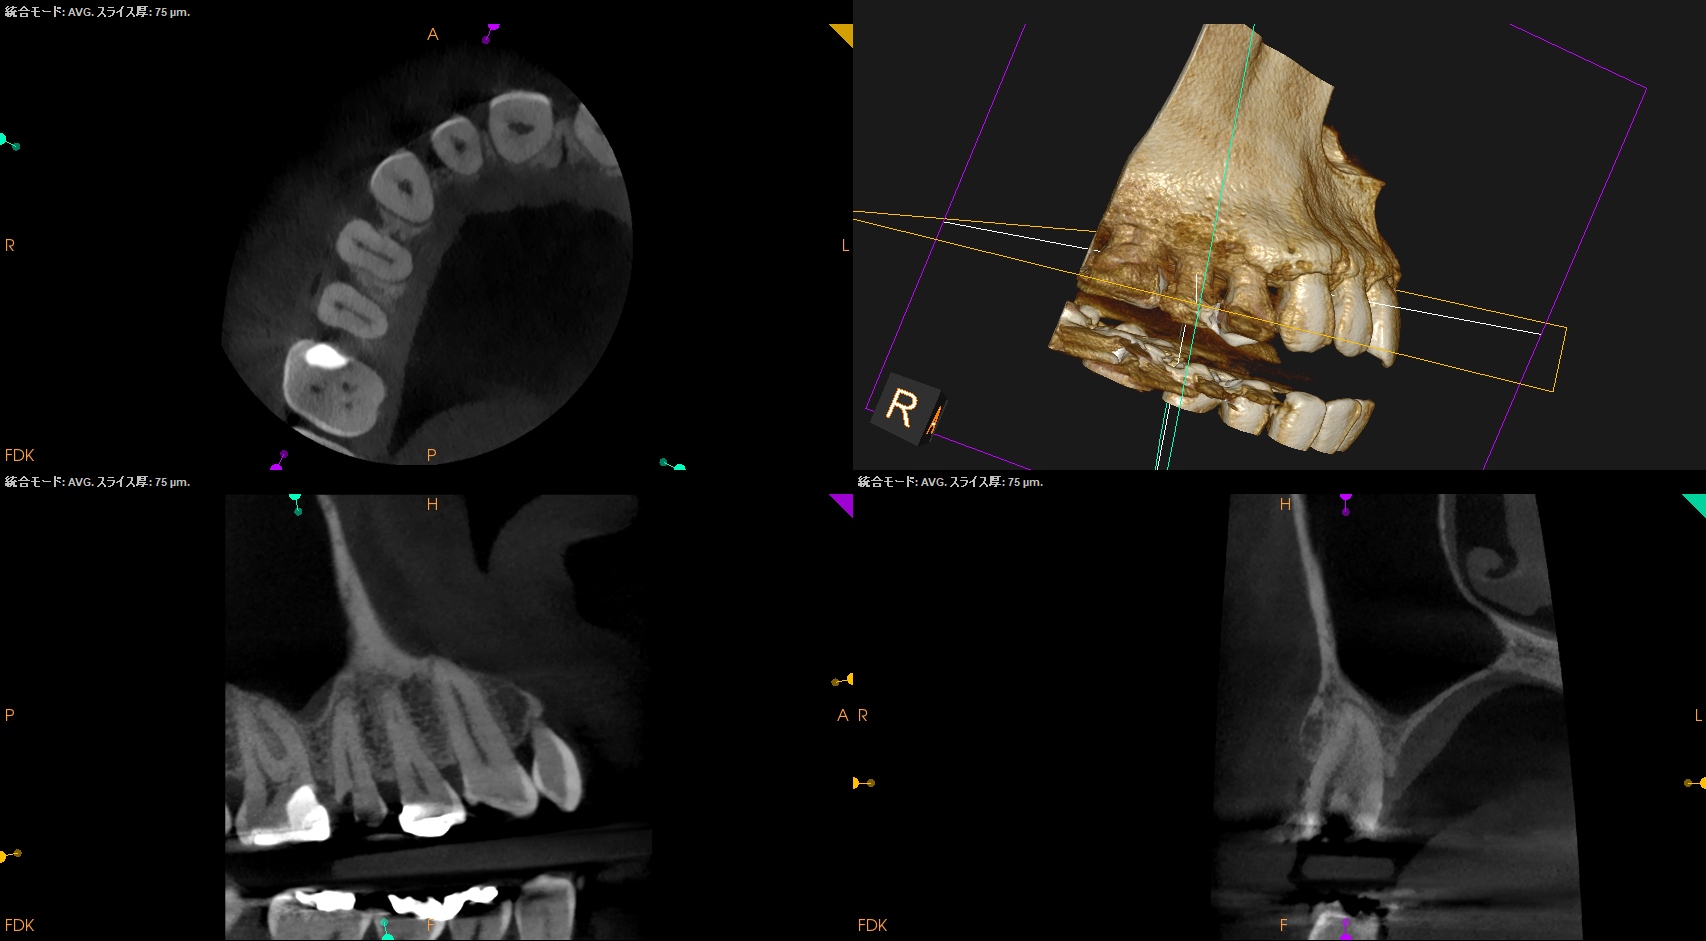

病変のない、Initial RCTだ。

Pulp Dx: Asymptomatic irreversible pulpitis

Periapical Dx: Symptomatic apical periodontitis

Recommended Tx: RCT

術後にPA, CBCTを撮影した。

問題はないだろう。